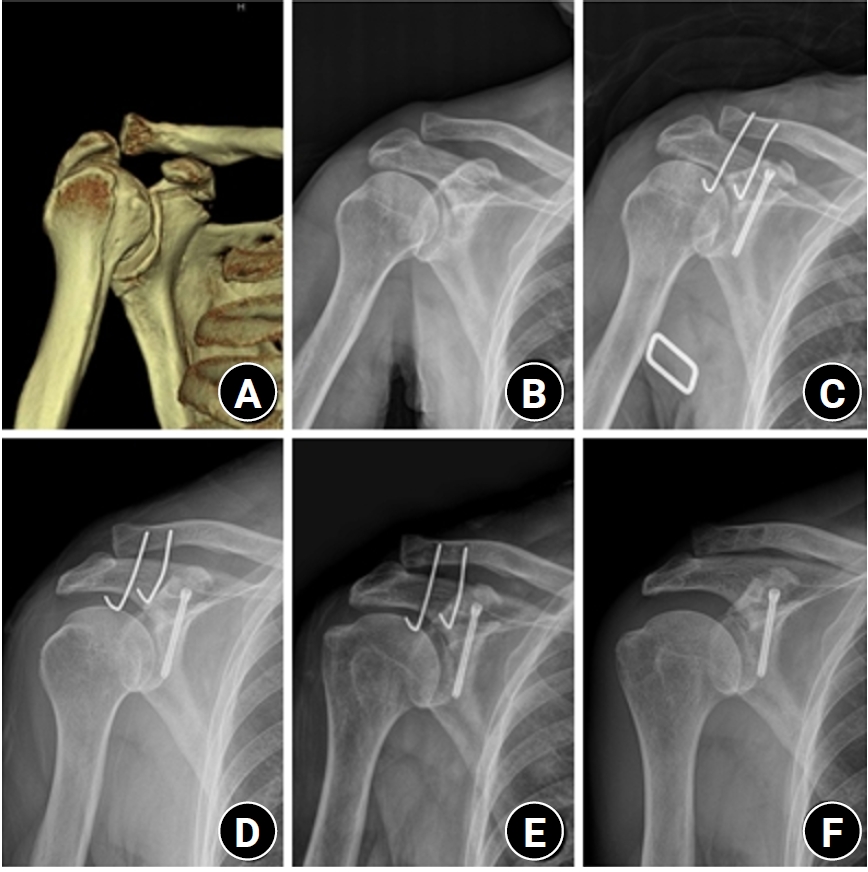

Three-dimensional computed tomography (A) and shoulder anteroposterior (AP) radiograph (B) of a 74-year-old male patient show a coracoid process fracture associated with an acromioclavicular joint (ACJ) injury. (C) A 3.0-mm headless compression screw was used for the coracoid process fracture, and two Kirschner (K)-wires were used for the ACJ injury. (D) Postoperative 2-week radiographs show K-wire deformation. (E) Postoperative 6-week radiographs show K-wire loosening. (F) Postoperative 6-month AP radiographs show nonunion of the coracoid process.

Fig. 2. Three-dimensional computed tomography (A) and shoulder anteroposterior (AP) radiograph (B) of a 74-year-old male patient show a coracoid process fracture associated with an acromioclavicular joint (ACJ) injury. (C) A 3.0-mm headless compression screw was used for the coracoid process fracture, and two Kirschner (K)-wires were used for the ACJ injury. (D) Postoperative 2-week radiographs show K-wire deformation. (E) Postoperative 6-week radiographs show K-wire loosening. (F) Postoperative 6-month AP radiographs show nonunion of the coracoid process.

No postoperative infections or neurovascular complications were observed in any of the patients. However, one patient experienced nonunion. The K-wire for ACJ fixation was removed at 6 weeks after the operation, and nonunion of the coracoid fixation was confirmed at the final follow-up of 6 months, but the patient's clinical outcome was good (Fig. 2).

Ogawa et al. [3] reported that among 80 cases of coracoid base fracture with concurrent injuries, 62 cases underwent surgical treatment and achieved bone union in all cases, resulting in satisfactory results. Of these, 17 cases were coracoid base fracture associated with the ACJ injury, and the mean age was 36 years. Fixation with screw and washer for coracoid fractures and transacromial fixation with K-wire for the ACJ dislocation was performed. Rhee et al. [16] showed in a comparative study on ACJ stabilization using K-wires transfixation versus locking hook plates fixation in the treatment of acute ACJ dislocation that the locking hook plate provided more stable than the K-wires. In this study, deformation and loosening of K-wires occurred in patients with nonunion, and clavicle hook plates were thought to be more effective than K-wires in preventing nonunion.